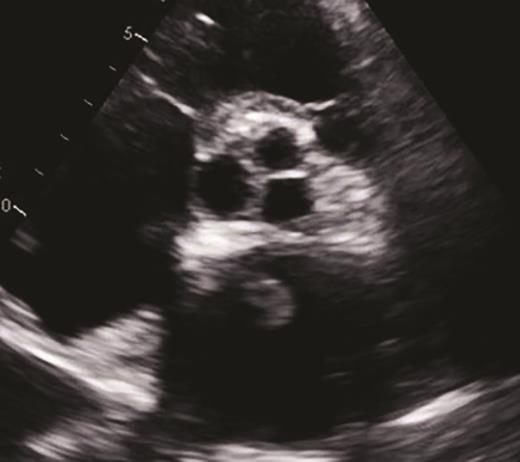

The patient’s hospital course in December 2019 was complicated by acute on chronic diastolic heart failure with preserved ejection fraction, new splenic infarct, acute lower extremity limb ischemia requiring revascularization, acute ischemic stroke involving the proximal inferior left M2 branch requiring mechanical thrombectomy, and a new lower extremity deep venous thrombus, all within a two-week period (Figure 3). After recovering from this hospitalization, the patient was started on treatment for AL amyloidosis with cyclophosphamide, bortezomib, and dexamethasone (CyBorD) in January 2020. Unfortunately, after one cycle of CyBorD, the patient developed gastrointestinal hemorrhage and recurrent stroke. A new left atrial thrombus was seen on TTE, despite ongoing anticoagulation with apixaban (Figure 4). The patient and family opted for comfort care at this time and the patient died shortly thereafter.

Short-axis view of a two-dimensional transthoracic echocardiogram demonstrating a new 1.5 × 1.0 cm echodensity (yellow circle) in the left atrium. This is compelling evidence by echocardiography indicating a thrombus.